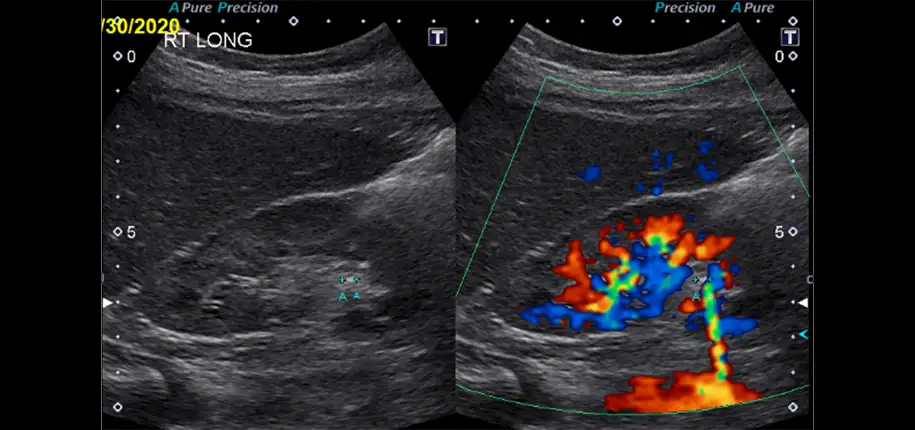

Abdominal or flank pain is a fairly common reason to go see a doctor or go to the emergency department. Kidney stones can be the cause of this symptom. Patients can also have blood in their urine, either visible or only microscopic. Imaging plays a big role in diagnosing kidney stones. A common modality to start off with is an ultrasound. Since ultrasound does not use ionizing radiation, it is especially attractive to use to image children. Additionally, children tend to be smaller than adults, which makes it easier for the sound waves to traverse the body for image production. Also, if the stone causes obstruction, ultrasound can show dilatation of the urinary tract.

However, ultrasound is not perfect and may miss some kidney stones. In a recent study performed by Cincinnati Children’s Hospital researchers, the sensitivity was found to be 67%. This means that 33% of kidney stones are not seen by ultrasound. This is especially true for older/larger patients. Therefore, if there is still a high clinical concern for kidney stones despite a normal ultrasound, a non-contrast CT scan should be considered. One should weigh the fact that CT scans use ionizing radiation, but if there is a good clinical reason to perform a CT scan, the benefit to the patient outweighs the risk. A non-contrast CT scan does not use IV contrast, so the patient does not need to have a peripheral IV in place. Actually, IV contrast can hide kidney stones as the brightness of the contrast agent is similar to that of stones.